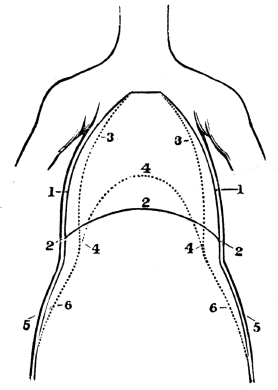

| 23. | Anatomy of the Respiratory Organs, | 209 |

| 24. | Physiology of the Respiratory Organs, | 217 |

| 25. | Hygiene of the Respiratory Organs, | 228 |

| 26. | Hygiene of the Respiratory Organs, continued, | 239 |

| 27. | Animal Heat, | 252 |

| 28. | Hygiene of Animal Heat, | 261 |